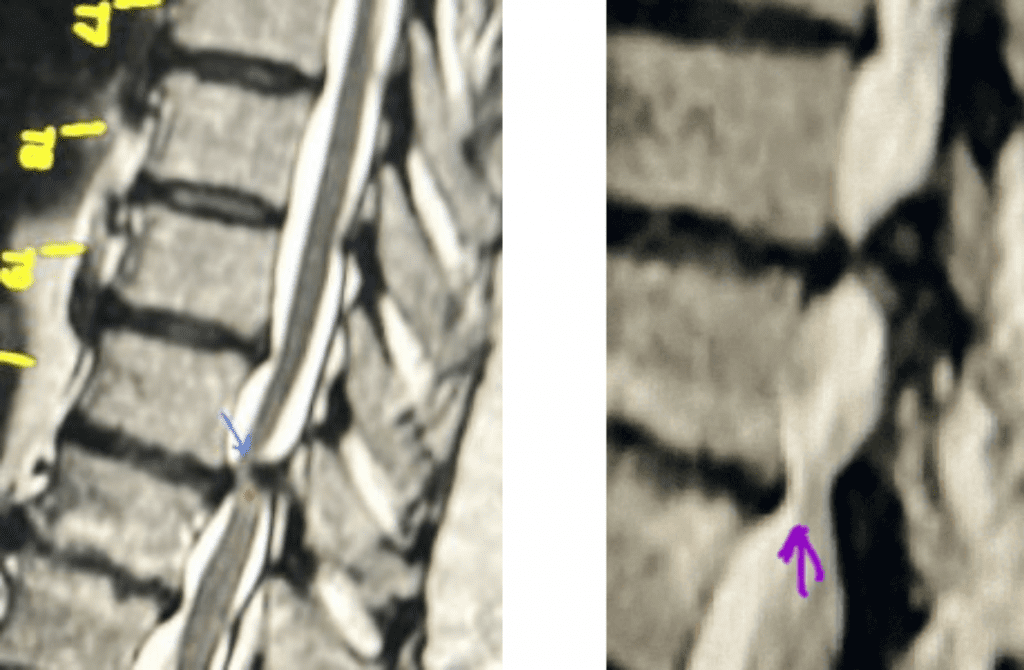

Figure 1. The sagittal MRIs demonstrate a very tight stenosis at T10-11 (blue arrow). Note the area of hyperintensity within the spinal cord at this level representing myelomalacia (red dot). Patient also has significant stenosis at T11-12 (purple arrow).

This 50-year-old morbidly obese female presents with one month of progressive weakness of her lower extremities. She also reported numbness and pain in her thighs. Her right leg was worse, and she had one episode of urinary incontinence. She had some back pain. She was ⅖ strength in her right hip flexor and quadriceps. She was ⅘ in her left lower extremity. MRI (Figure 1 and Figure 2) revealed very tight stenosis circumferentially at T10-11 secondary to facet hypertrophy and anterior disc osteophyte complex with associated myelomalacia of the spinal cord. There was also stenosis to a lesser degree but still significant at the T11-12 level.